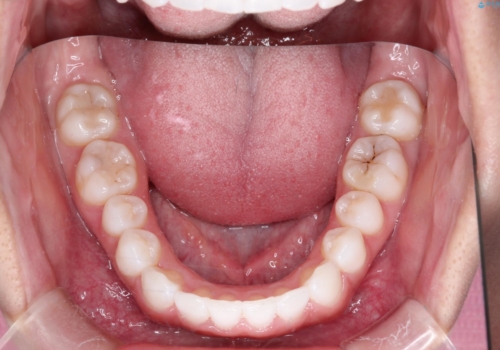

インビザラインを用いた叢生(歯並びのガタつき)の治療

- 初診時には前歯部に捻転や叢生、臼歯部にも一部叢生が見られる状態でした。

インビザラインでの治療を計画し、行っていきました。

インビザライン治療により、捻転を含む歯列もしっかりと改善しています。

基本的な不正咬合部分は初回の30枚のマウスピースでほぼ改善しており、リファインメントでは前歯部の細かな調整など、患者様の要望を取り入れる形でシミュレーションをセットアップし、満足の行く結果に仕上がりました。